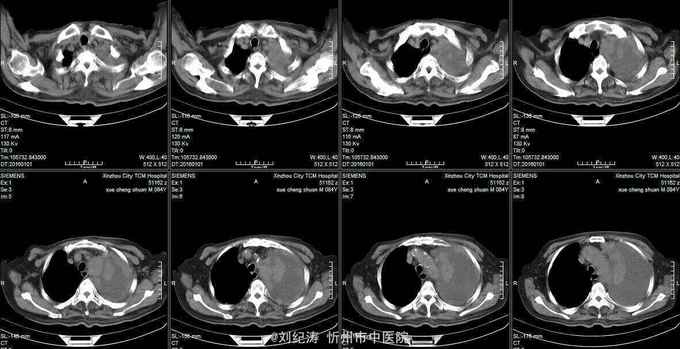

查体:ECOG评分:3分,生命指征平稳,浅表淋巴结未触及明显肿大,双眼睑无水肿,唇无发绀,颈软,双侧胸廓对称,左肺语颤增强,左肺呼吸音消失,右肺呼吸音粗,可闻及哮鸣音,心律齐,腹平软,肝脾肋下未触及,移动性浊音阴性,肠鸣音3次/分,双下肢无水肿。 辅助检查:血常规(2016.1.1):WBC:10.6*109/L,RBC:4.69*1012/L, PLT:165*109/L ,HGB:167g/L.生化(2016.1.1):谷丙转氨酶11U/L,谷草转氨酶11U/L,总蛋白60g/L,白蛋白33g/L,尿素:9.8mmol/L,肌酐:123umol/L,尿酸:251 umol/L,血糖:7.37 mmol/L;电解质:钾:4.79mmol/L,钠:123.5 mmol/L,氯:85.7 mmol/L,钙:2.03 mmol/L。肺部CT(2016.1.1):左肺完全萎缩,左侧胸腔大量积液,右肺未见异常,纵膈轻度右移,未见明显肿大淋巴结。